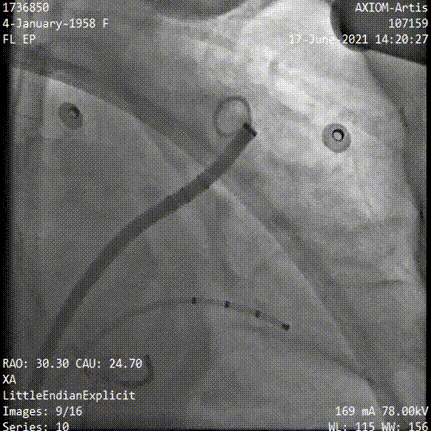

RAO30 CAU25

RAO30° CAU25°造影,左心耳形态充分暴露,可以观察到心耳属于反鸡翅形状。内部梳状肌较发达,深度较浅。

DSA测量开口17mm,深度19mm,与CT测量结果类似,考虑选择24mm watchman封堵器,首选X3轴向进行封堵。